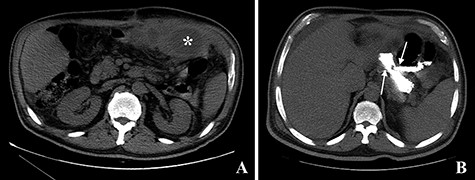

In December 2015, the patient presented to the emergency room complaining of pain in the left hypochondrium and anorexia. Upon physical examination, the only abnormal finding was tenderness to palpation of the left hypochondrium. The laboratory tests revealed an elevated white blood cells count (18.88 × 103/μL) and an elevated C-reactive protein (263.66 mg/L). A CT scan of the abdomen revealed a GGF with an associated abscess (see Fig. 8).

Computed tomography images. A: Image obtained prior to administration of contrast showing an abscess on the left upper quadrant of the abdomen (asterisk). B: Image obtained after administration of oral contrast showing progression of contrast through the gastro-jejunal anastomosis and through the gastro-gastric fistula (arrows).